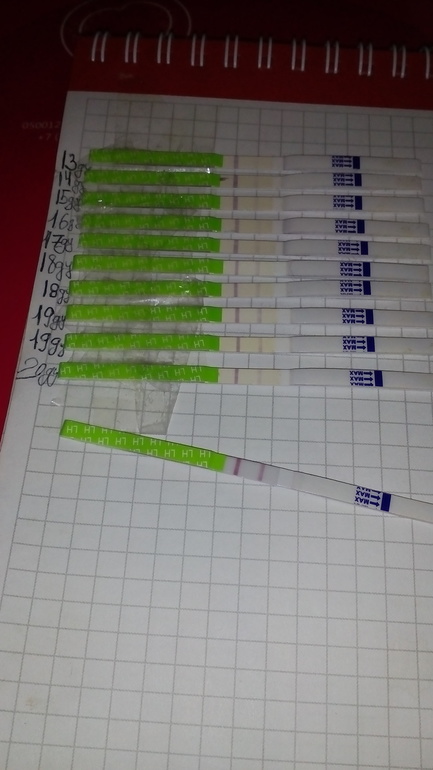

Девочки кто разбирается?была ли о? есть ли шанс на б в этом цикле?

Девочки кто разбирается?была ли о? есть ли шанс на б в этом цикле?

Скажите пожалуйста девочки это О? Или ещё должна быть темнее?